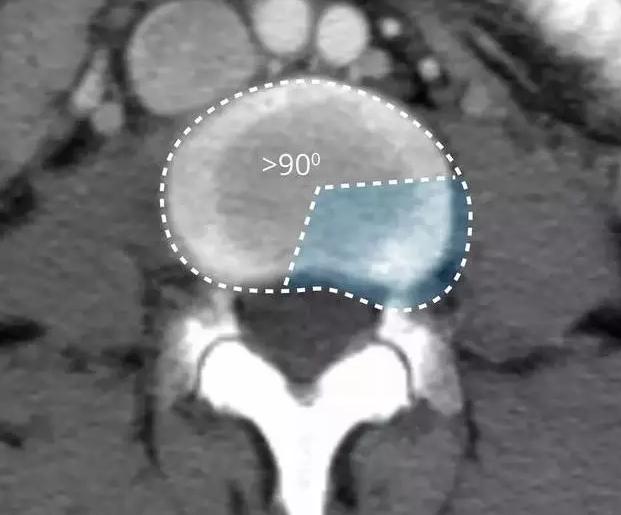

随着年龄的增长或外伤等原因,导致纤维环发生变形或损伤,但是纤维环还没有破碎,外面还是光滑的,只是整体上被压扁了很多,所以俯视看,椎间盘变的膨大了,这就是椎间盘的膨出。

在影像学上表现为纤维环均匀的超出椎体终板边缘。